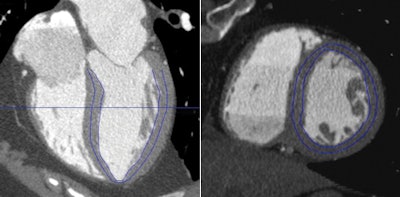

| Images are from a 60-year-old woman with obstructive coronary artery disease in the left anterior descending and left circumflex territories. A time-volume analysis tool was used to evaluate subendocardial attenuation. Automated left ventricular wall segmentation is adjusted manually to select subendocardium (blue outline), as shown in horizontal long-axis (left) and short-axis (right) views. Images courtesy of AJR. |